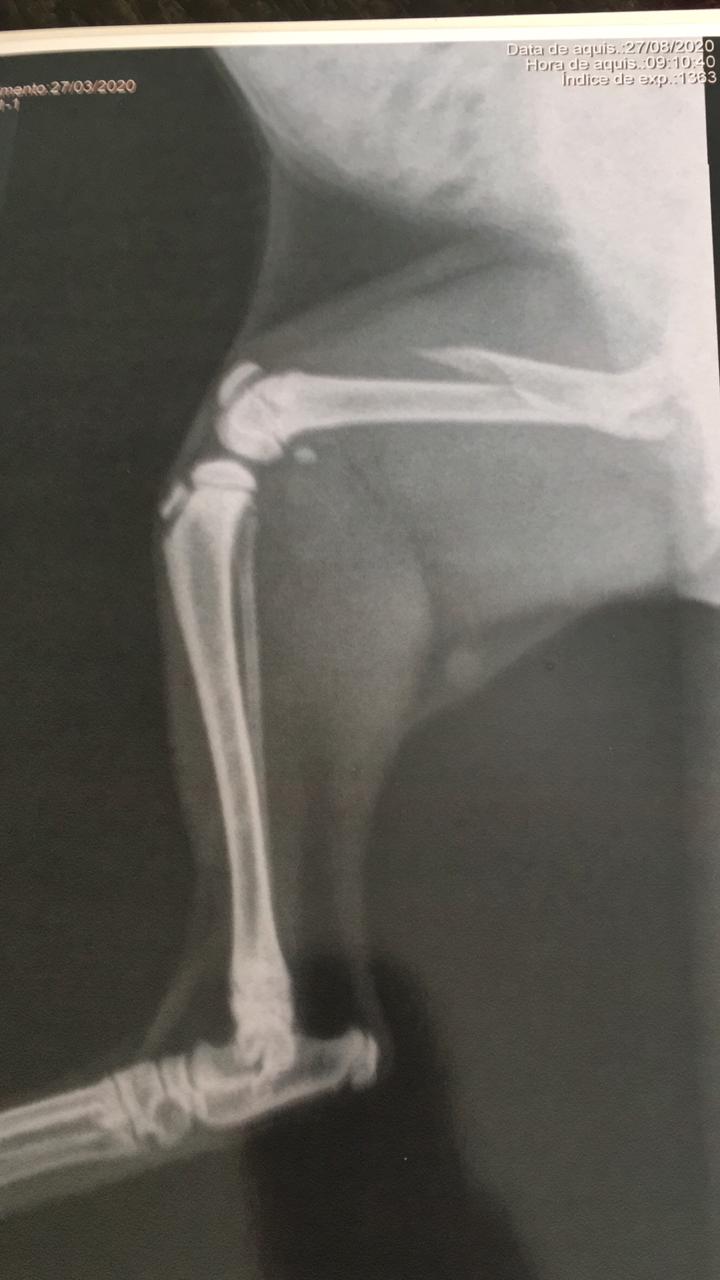

A senhora Regina Oliveira, residente na Rua Edval Porfírio, no Monte Castelo, está pedindo ajuda para realizar uma cirurgia em um gatinho que tem apenas cinco meses de vida e que na quarta-feira passada (26/08) foi acidentado, ficando com uma fratura no fêmur.

A cirurgia do gatinho Théo custa R$ 1.600,00. “Por favor, se poderem, me ajude. O bichinho está sentindo muita dor e eu não tenho como arrumar esse dinheiro”, disse ela.